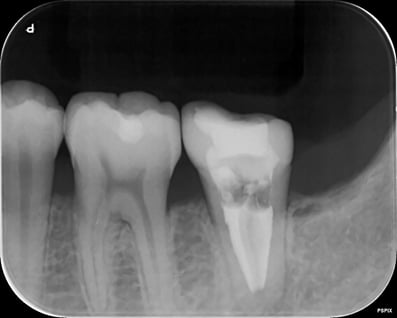

歯根の周囲には、歯根を取り巻くようなX線透過があります。(炎症があるということです)

根管の中には、ガッタパーチャという天然ゴムの根管充填材がありますが、これが緊密に歯根の尖端まで充填(詰め)されていないので、このような状態となっています。まずは、このガッタパーチャを完全に除去することが重要です。